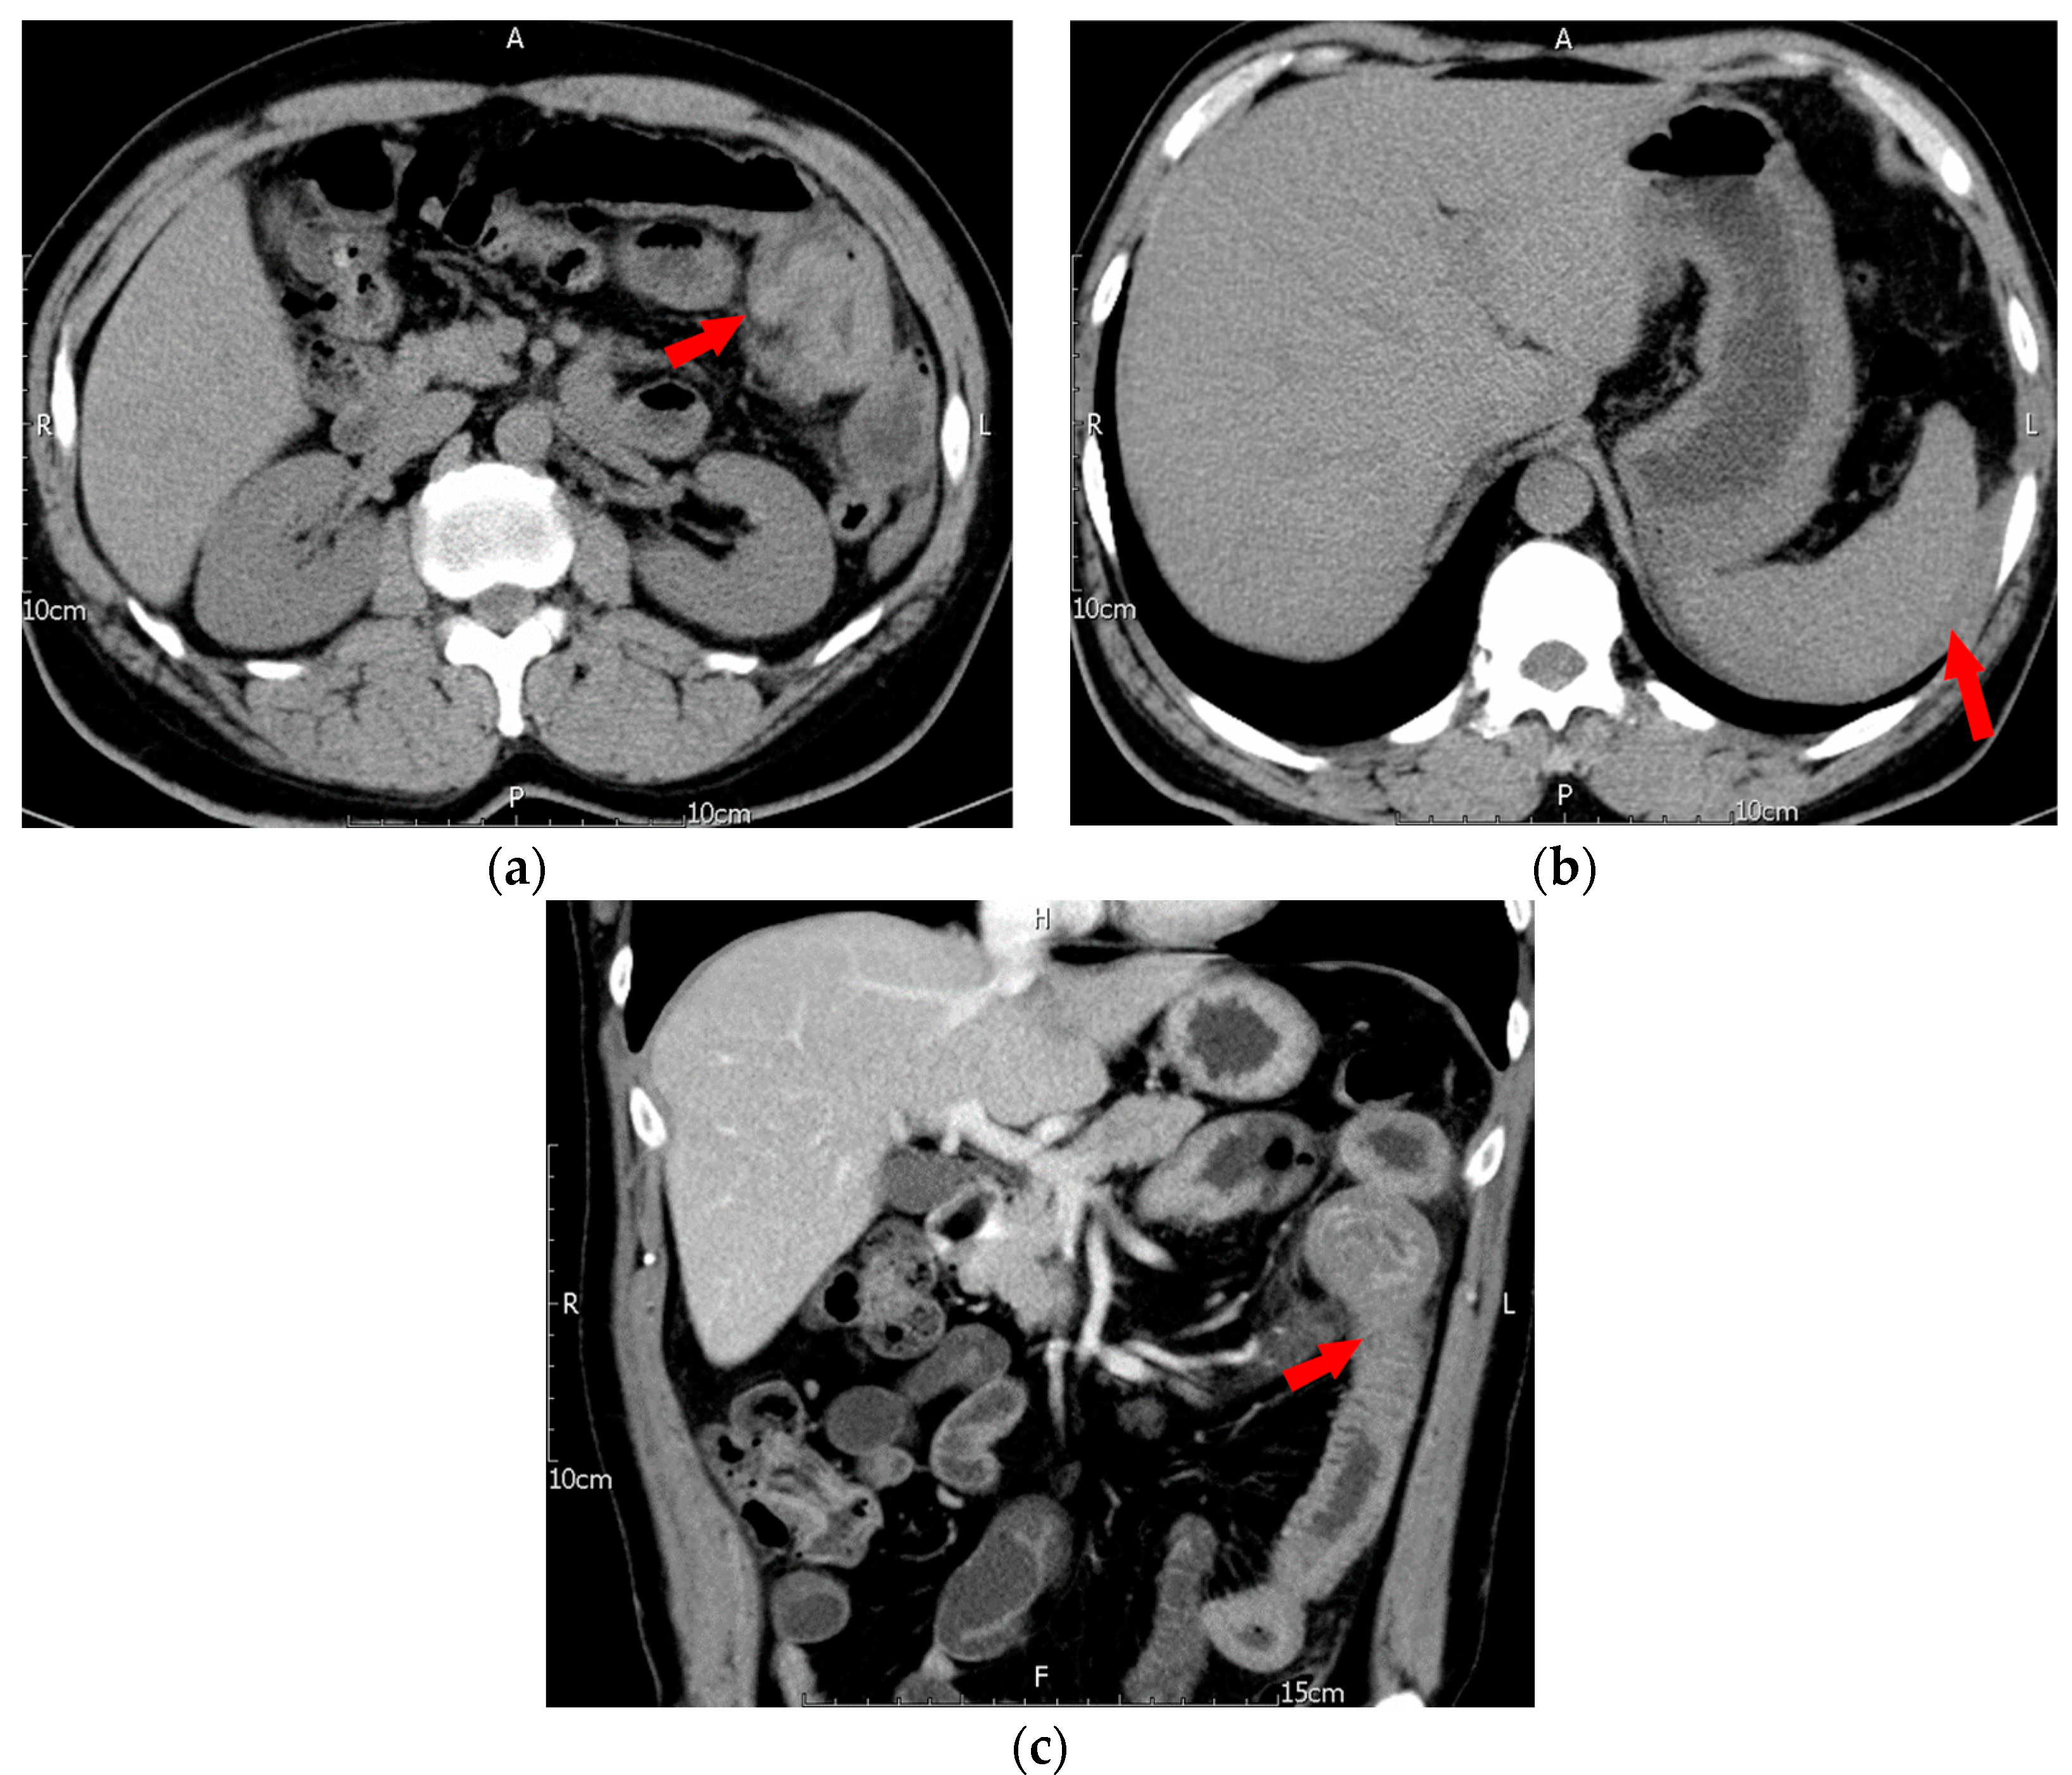

In late June 2019, this patient, with a body weight of 70 kg, was admitted to the emergency department with a complaint of generalized abdominal pain that had persisted for 3 days. The pain was mainly located on the left side and in the periumbilical regions. Associated symptoms included decreased appetite and nausea, but the patient did not have a fever. The patient had experienced tarry stool one day before admission. The patient had no history of trauma. On physical examination, the patient had periumbilical tenderness and rebound tenderness. Lab data revealed leukocytosis (WBC: 13,170/µL) with neutrophil predominance, an elevated C-reactive protein (CRP) level of 5.09 mg/dL, and a normal hemoglobin (Hb) level (Hb: 14.9 g/dL). Platelet count was normal at 398 × 103/µL. His prothrombin time/international normalized ratio (PT/INR) was normal at 1.14 but activated partial thromboplastin time (aPTT) was prolonged at 146.3 s (control: 32–45 s). Under the suspicion of acute abdomen, a computed tomography (CT) of the abdomen was performed, revealing bowel wall thickening in a wide segment of the jejunum, consistent with an intramural hematoma and an intussusception-like lesion in the jejunal region. Further, there was ascites with hyperdense layering noted in the perisplenic and subphrenic areas and the cul-de-sac, consistent with hemoperitoneum (Figure 1).

Figure 1.

First episode of intramural hematoma of jejunum. (a) Axial non-contrast CT showed marked segmental wall thickening of the proximal jejunum with diffuse hyperdensity (arrow), (b) axial non-contrast CT showed perisplenic hemoperitoneum (arrow), (c) coronal reformatted contrast-enhanced CT showed contrast enhancement of the inner mucosa, but there was no contrast enhancement of the thickened wall of the corresponding proximal jejunum, which indicated the presence of an intramural hematoma (arrow).